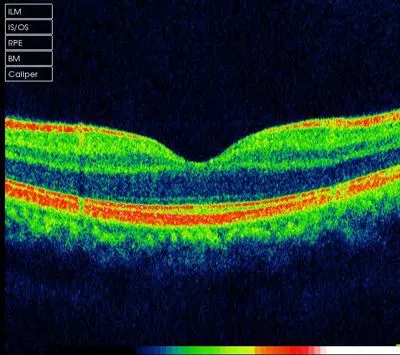

方法2:五十歲以上老年人定期做眼底OCT檢查,就可以知(zhī)道黃斑區有哪些早期的病變了。

正常黃斑的眼底OCT圖像